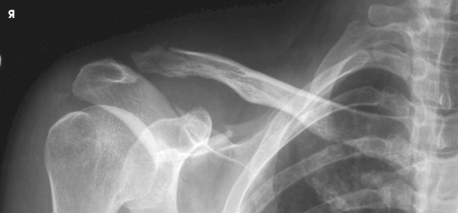

This projection is recommended for acute shoulder trauma and for identifying posterior scapulohumeral dislocations, glenoid fractures, Hill-Sachs lesions, and soft tissue calcifications.1

Structures shown: The scapulohumeral joint, humeral head, coracoid process, and scapular head and neck are shown (Fig. 5-49).

Fig. 5-49 AP axial oblique: Garth method showing anterior dislocation of proximal humerus. Humeral head is shown below coracoid process, a common appearance with anterior dislocation. (Courtesy Bruce W. Long, MS, RT[R][CV], and John A. Rafert, MS, RT[R].)